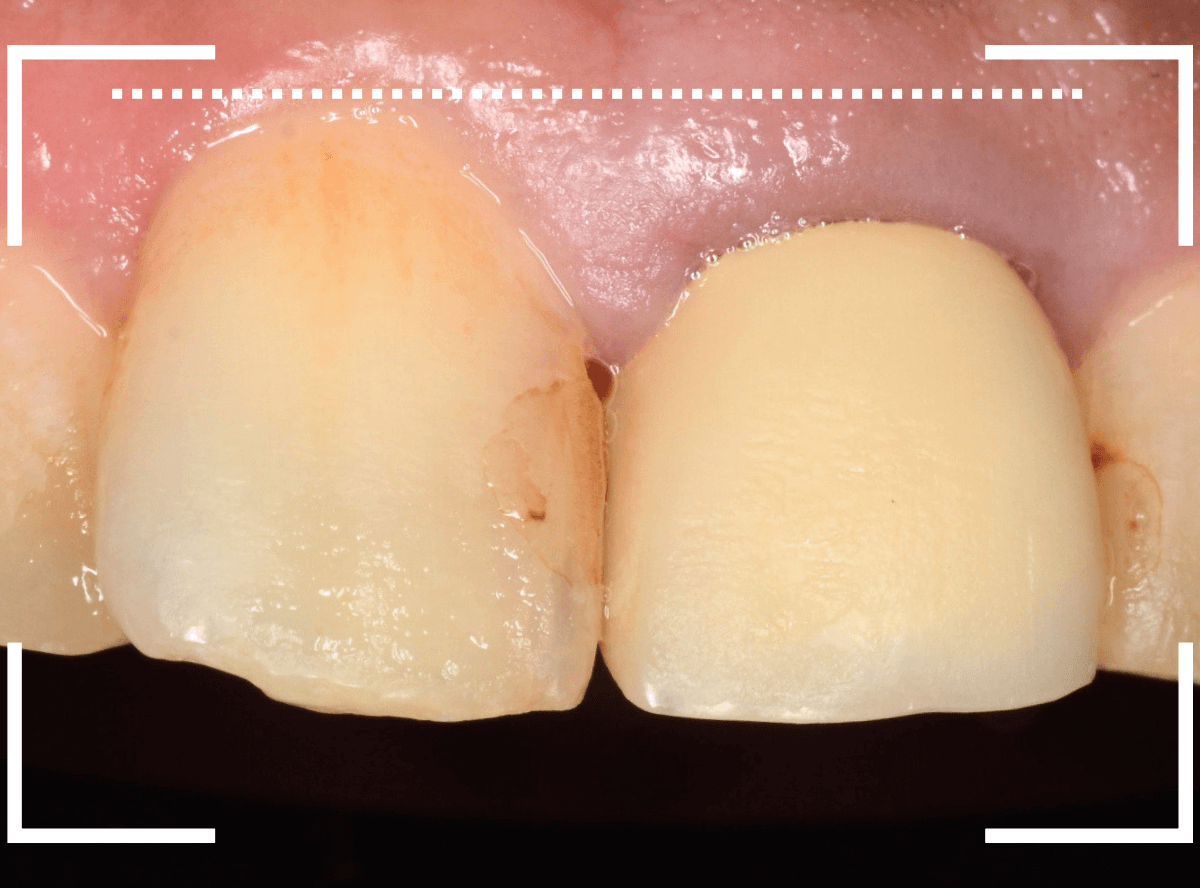

Case.14 劣化した保険治療のさし歯(レジン前装冠)をジルコニア・セラミックへ

上の前歯を綺麗にやり直したい、という希望の患者さんです。

拝見すると、古くなった保険診療でのレジン前装冠が入っていました。

色も劣化して全体にのっぺりした感じになってしまっています。

審美性の高い、ジルコニアセラミックでのやり直しをご提案し、患者さんも選択されました。

まず、レジン前装冠を除去します。

すると、前後の歯に虫歯が見つかりましたので、先に治療する事になりました。

前後の虫歯を除去しました。手前の歯はそこそこ虫歯になっていました。